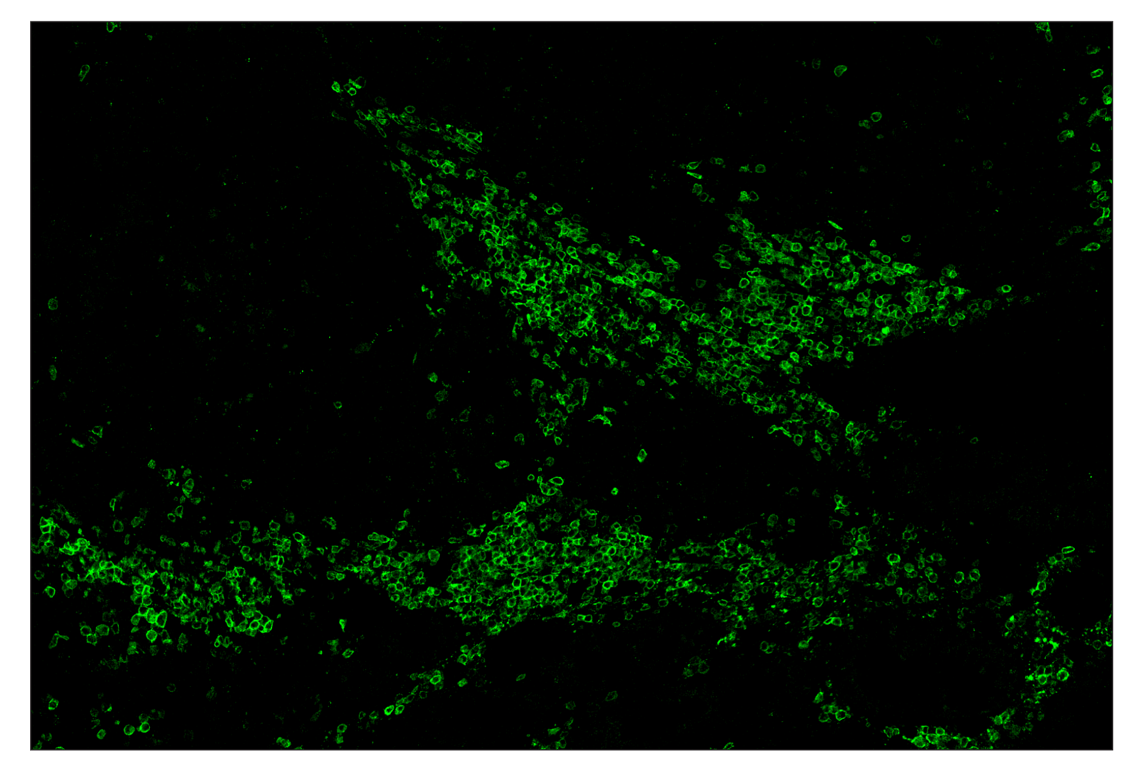

CD19 (Intracellular Domain) (D4V4B) & CO-0054-750 SignalStar Oligo-Antibody Pair #80028

CD19 (Intracellular Domain) (D4V4B) Rabbit Monoclonal Antibody (SignalStar™ Conjugate 0054) recognizes endogenous levels of total CD19 protein.

Human, Mouse